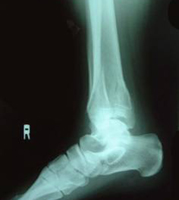

X線所見:脛骨は正面像で下端部の骨折が認められ、末梢骨片は後外方へ転位していた。中枢骨片は側面像で前下方への転位を認めた。腓骨は下端部で斜骨折を認めるが、転位は認めなかった。

初診時の写真・X線

レントゲンの矢印が骨折線を示す